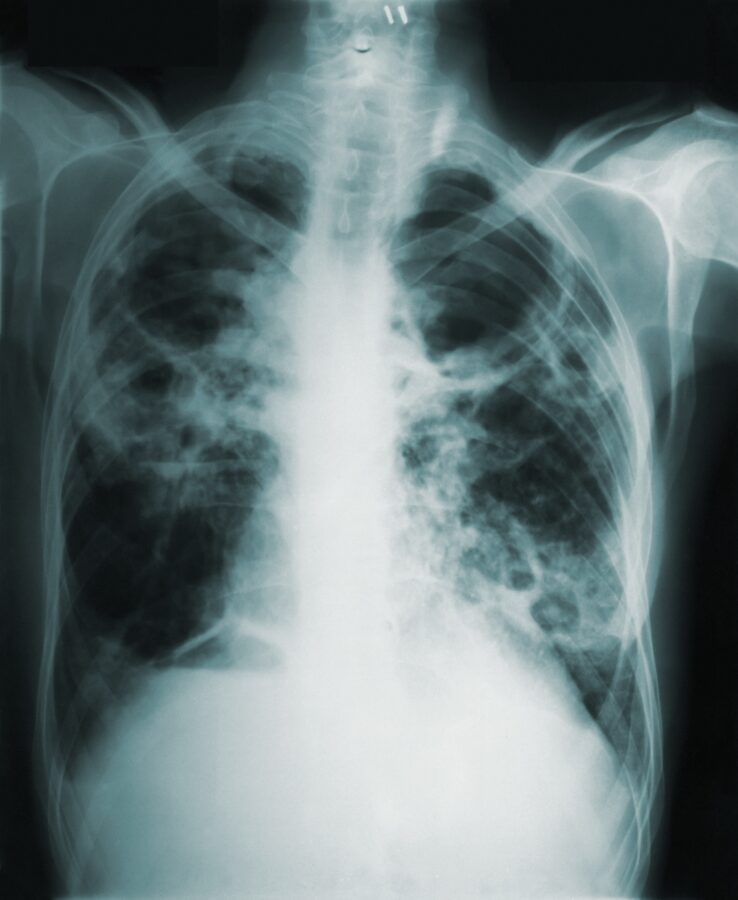

Pleural infection is a common and severe condition in which fluid builds up between the lungs and the chest due to a bacterial infection. Identifying the bacteria causing pleural infections is critical in choosing the correct antibiotics. Currently, by trying to culture bacteria from the fluid, doctors only identify the responsible bacteria in 60% of cases. We suspect bacteria that are difficult to grow, such as Legionella – the cause of Legionnaires’ disease, might be responsible. In Canterbury, Legionnaires disease is common – with among the highest rates in the world. We think it could also be a common cause of pleural infection.